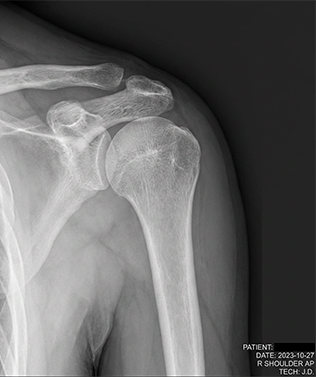

Exames complementares podem ser solicitados, como:

- Radiografia